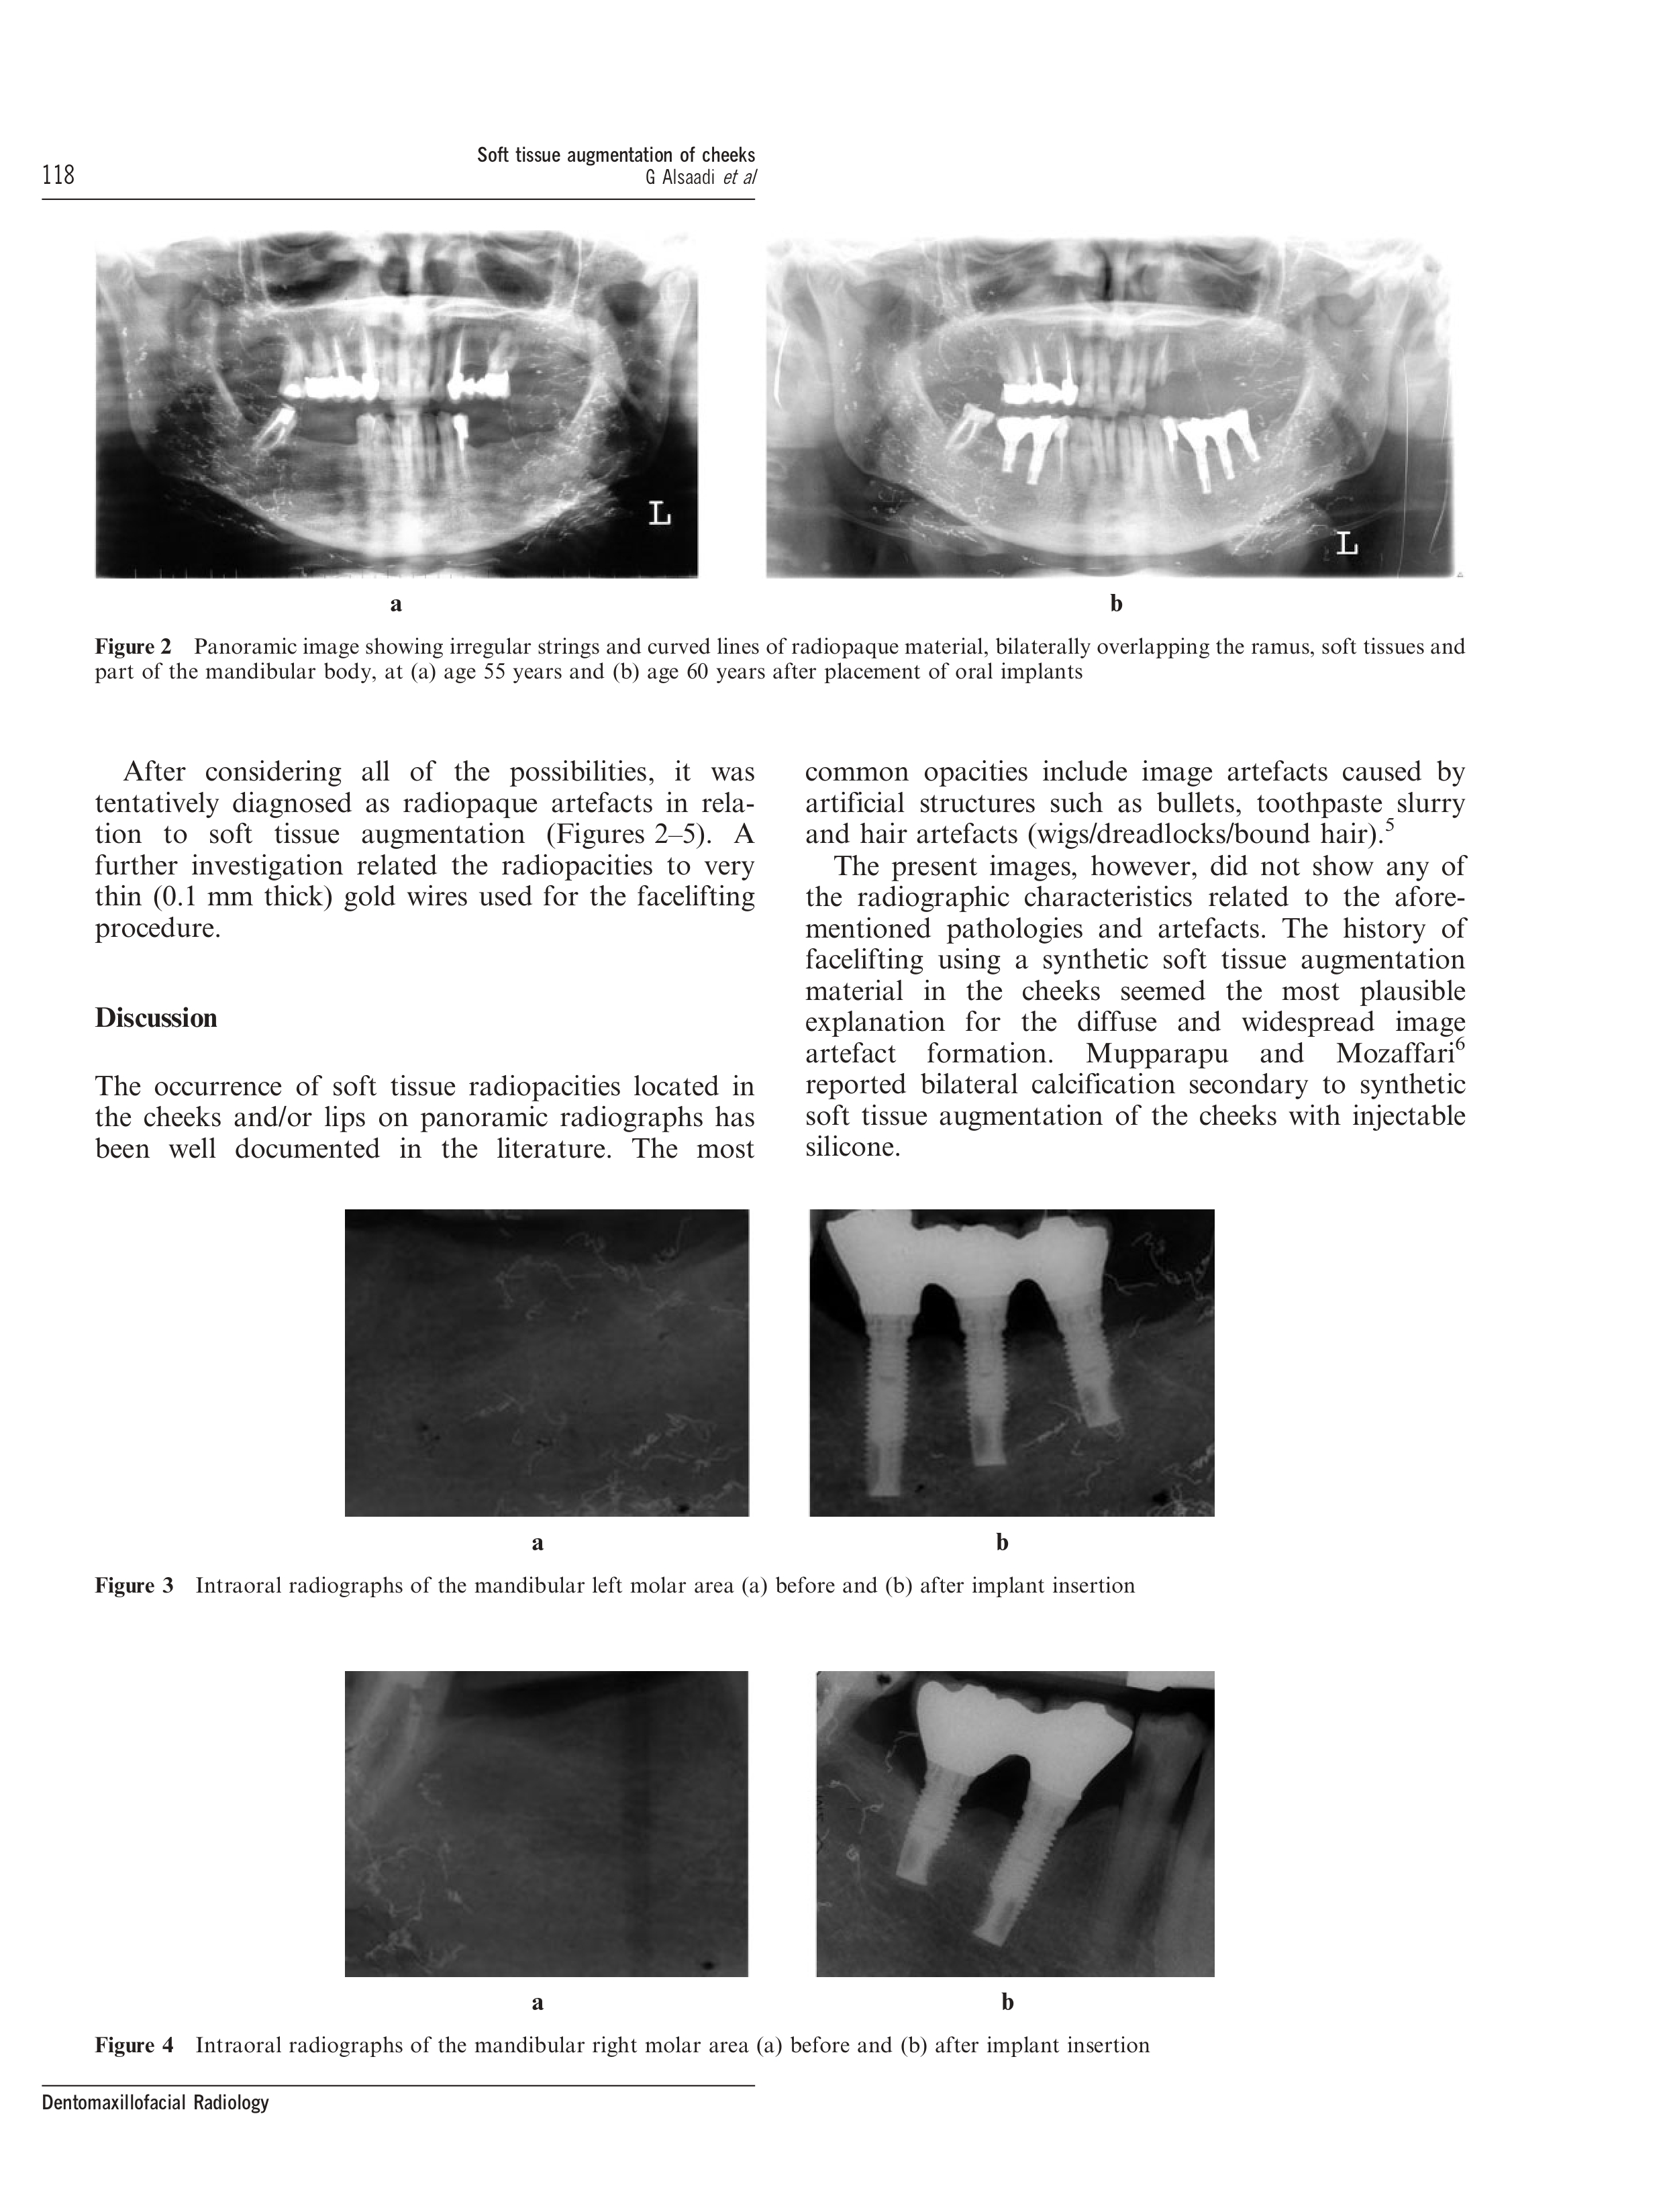

Soft tissue augmentation of the cheeks detected on intra- and extraoral radiographs: a case report